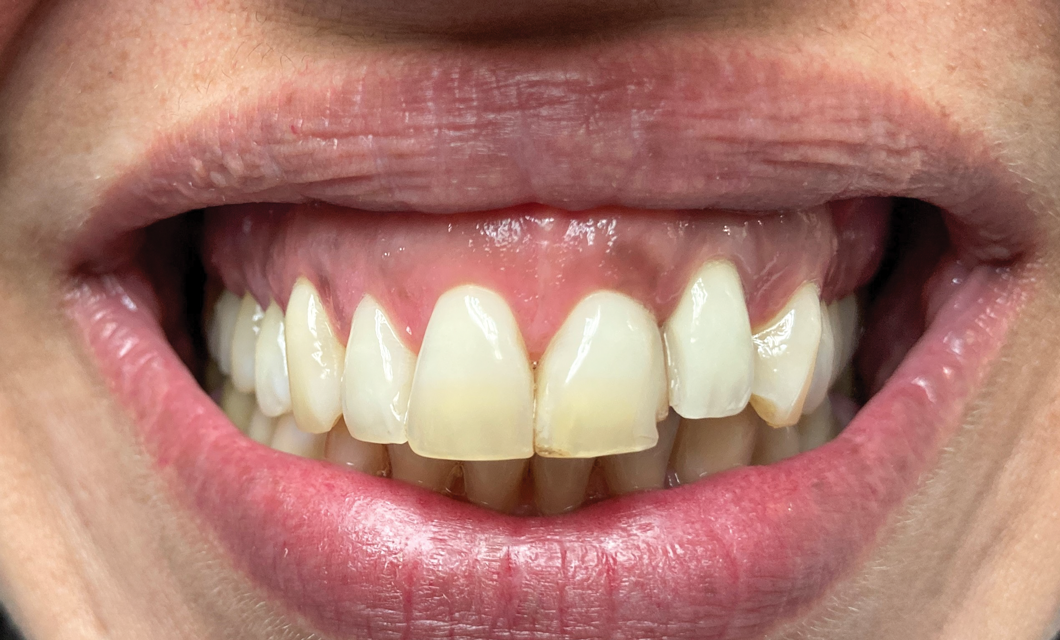

Fig 4. Skeletal growth can affect the esthetic zone at any age. A 35-year-old woman with a missing central incisor (No. 8) due to trauma was restored with an implant. Ten years later, as shown, a small discrepancy between the occlusal planes of the two central incisors due to continued skeletal growth can be noticed.

Figure 4

Further investigations of a crown's submersion risk among adults showed that significant skeletal dimensional changes as well as continuous eruption of teeth can occur later in life also (Figure 4).30 Such findings prompted researchers to follow-up single implant-supported prosthesis cases of different age populations for various time periods. Over an 8-year period, Thilander et al followed 15 adolescents who had single implant-supported crowns placed in the anterior maxilla.29 They reported no implant loss as well as an acceptable esthetic appearance in most subjects at the end of the observation period; however, eruption of the adjacent natural teeth continued and resulted in infraocclusion of the implant-supported crowns in some patients, as well as reduction of marginal bone level around some teeth adjacent to the implants. The authors specified that the infraocclusion was mainly found where incisor contact was absent meaning that good incisor stability is of utmost importance before an implant is placed in the esthetic area. Additionally, the authors tracked a single implant-supported crown placement in the upper incisor area of three adults and observed infraocclusion years after installation. They concluded that infraocclusion might occur in adulthood also and no chronological age is considered safe from such skeletal changes. In the adolescent group, the main vertical marginal difference occurred during the first 3 years of follow-up, which corresponded to the overall body growth of the individual. Still, infraocclusion further continued in 10 individuals during the subsequent years, despite body growth cessation. In a case report by Rossi and Andreasen, unfavorable clinical and radiographic findings were demonstrated over a 15-year period after a single tooth replacement by dental implants.25 In addition to the 9 mm discrepancy between the implant collar and the cementoenamel junction of the adjacent central incisor, the authors found that the maxilla significantly resorbed on the labial aspect during the skeletal facial vertical growth.

Based on clinical findings among young populations, it has been suggested that the most appropriate time for implant placement is the age when skeletal growth is finalized,31,32 which corresponds with the termination of general skeletal growth. However, the orthodontic literature has disclosed that facial growth actually continues throughout life (Figure 4),33 and therefore, at present, it is recognized that no decision as to the right time to place implants in the esthetic area is definite, and each case should be discussed with the patient and/or, in the case of adolescents, the parents as well.

Most case reports discussed infraocclusion following single implant-supported crown placement in adolescents and young patients. Cocchetto et al demonstrated that facial skeletal growth does not stop after adolescence but continues into adulthood.27 Therefore, the timing of esthetic treatment that includes single implant placement next to natural teeth should be carefully considered and discussed with the patient. In a retrospective evaluation of implant-retained crowns in the anterior maxillae of adult patients during a 20-year span, 73% of recalled patients displayed infraocclusion. There was no statistical difference between the younger (<30) and older (>30) groups. When evaluating their awareness and perception of the problem, most of the patients were unaware of the change, or if they were aware, they showed no interest in changing the situation. No predisposition risk factors have been identified for this potentially frustrating situation.34